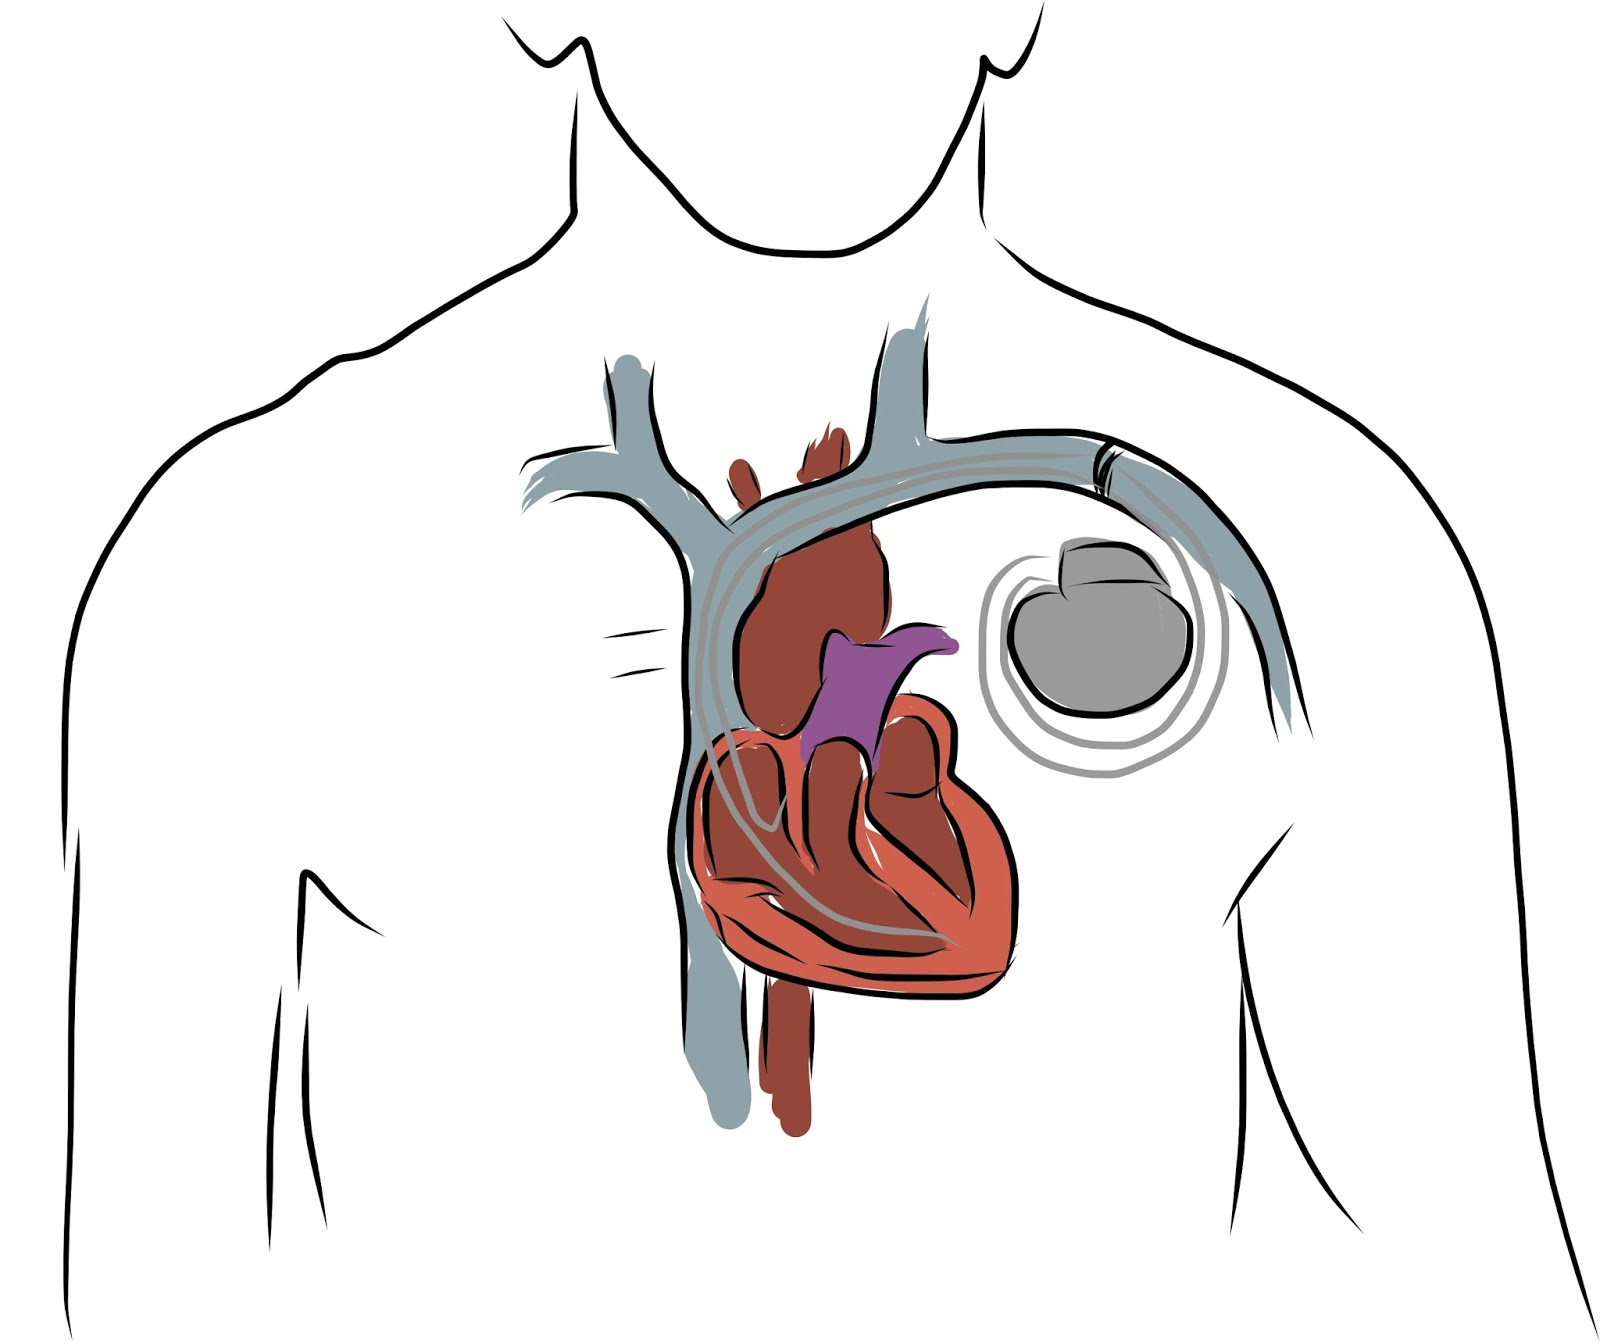

Nei giorni scorsi a Pisa è stato effettuato con successo il primo impianto del più piccolo pacemaker senza fili al mondo. L’impianto rientra nello studio clinico mondiale Micra ed è stato effettuato, per la prima volta in Italia, da Maria Grazia Bongiorni, direttore dell’Unità operativa di Cardiologia 2 dell’Aoup-Azienda ospedaliero-universitaria pisana, coadiuvata dalla sua équipe. L’assessore al diritto alla salute della Regione Toscana, Luigi Marroni, ha espresso grande soddisfazione per questo impianto e si è congratulato con la dottoressa Bongiorni e con l’intera équipe che ha eseguito l’intervento, sottolineando che l’azienda ospedaliero-universitaria pisana è uno dei pochi centri al mondo che partecipano a questo studio.

Nei giorni scorsi a Pisa è stato effettuato con successo il primo impianto del più piccolo pacemaker senza fili al mondo. L’impianto rientra nello studio clinico mondiale Micra ed è stato effettuato, per la prima volta in Italia, da Maria Grazia Bongiorni, direttore dell’Unità operativa di Cardiologia 2 dell’Aoup-Azienda ospedaliero-universitaria pisana, coadiuvata dalla sua équipe. L’assessore al diritto alla salute della Regione Toscana, Luigi Marroni, ha espresso grande soddisfazione per questo impianto e si è congratulato con la dottoressa Bongiorni e con l’intera équipe che ha eseguito l’intervento, sottolineando che l’azienda ospedaliero-universitaria pisana è uno dei pochi centri al mondo che partecipano a questo studio.

Nei giorni scorsi a Pisa è stato effettuato con successo il primo impianto del più piccolo pacemaker senza fili al mondo. L’impianto rientra nello studio clinico mondiale Micra ed è stato effettuato, per la prima volta in Italia, da Maria Grazia Bongiorni, direttore dell’Unità operativa di Cardiologia 2 dell’Aoup-Azienda ospedaliero-universitaria pisana, coadiuvata dalla sua équipe. […]